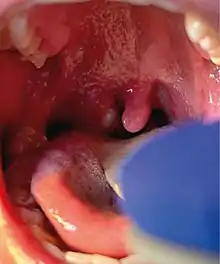

Right tonsillar enlargement with an overlying pustular lesion during the outbreak

Unusually, none of these new cases had any known contact history with the previous three confirmed cases, which suggested a kind of transmission that had not been seen before,[69] a wider community transmission of the virus in the London area. The UKHSA stated that the risk to the general public remained "very low".[68][70] Patients with active mpox infection were confirmed to be hospitalised at the Royal Victoria Infirmary in Newcastle upon Tyne and at the Royal Free Hospital and Guy's Hospital in London.[68]